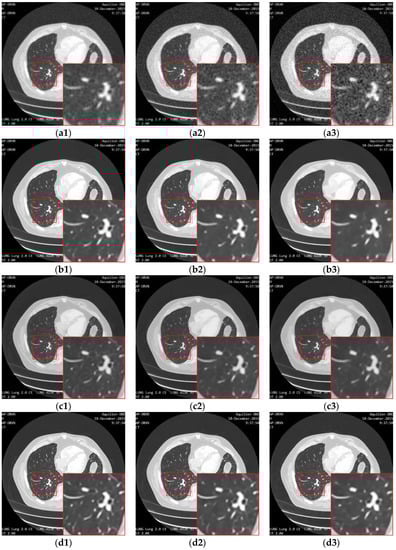

Figure 14 shows the result of enhancing the quality of images corrupted by noise and low-resolution through different methods. The bicubic interpolation method provides the worst performance, with much remaining noise and artifacts along the edges in the high-resolution image. This is mainly because the bicubic method simply makes use of the intensities in the neighborhood without taking the structure information into account. When the noise is distributed around the image, the noise intensities are also calculated by the interpolation function in the high-resolution image, resulting in the artifacts and blurring as shown in Figure 14(c1–c3). The deep learning methods perform better than the classic interpolation method because they make use of the visual features of the image so that the noise can be eliminated. However, the SRMD needs to know the noise level as prior knowledge. When the actual noise is different from the assumed noise, the performance is not as convincing. In our experiment, the noise level is unknown and was set by the user blindly, so it can be considered in Figure 14(d1–d3) that the structures, edges, or other details are not reconstructed in the resulted image. As shown in Figure 14(e1–e3), the SRCGAN can recover the structures in the medical image well, but some noise cannot be eliminated well because the GAN may consider this noise as tiny structures by mistake. In contrast, as shown in Figure 14(f1–f3), the RED-CNN can provide a good performance in the removal of noise because the U-net structure can filter out the noise features very well. However, it will over-smooth small edges in the image because it lacks the ability to preserve detailed information and perceptual features. As shown in Figure 14(g1–g3), the RDN method performs better than the previous methods because the residual-dense block can extract and reuse the image features better than the simple convolution layer used in the SRMD, SRCGAN, and RED-CNN. However, noise remains in the high-resolution image due to the ability of the skip connection to transfer noise features to the last fully connection layer as well as the structure features. Moreover, the RDN also needs to have prior knowledge of the noise level in the image, which makes it unable to adapt to a blind case. Our proposed method takes advantage of the RDN method and improves it by embedding an inception block into the skip connection routines. Moreover, it makes use of the noise estimation network to automatically calculate the noise level and takes that as the input of the quality enhancement network. Therefore, as shown in Figure 14(h1–h3), the proposed framework provides superior performance on noise removal and detail preservation during the super-resolution.

Figure 14.

The result of enhancement of the quality of images corrupted by noise with different levels and low-resolution through different methods. (a1), (a2) and (a3) are the input images with noise level 5, 10 and 15. (b1), (b2) and (b3) are the ground truth image. (c1), (c2) and (c3) are the images (a1), (a2) and (a3) processed by the bicubic method. (d1), (d2) and (d3) are the images (a1), (a2) and (a3) processed by the SRMD method. (e1), (e2) and (e3) are the images (a1), (a2) and (a3) processed by the SRCGAN method. (f1), (f2) and (f3) are the images (a1), (a2) and (a3) processed by the RED-CNN method. (g1), (g2) and (g3) are the images (a1), (a2) and (a3) processed by the RDN method. (h1), (h2) and (h3) are the images (a1), (a2) and (a3) processed by the proposed method.

Table 4 shows the values of PSNR and SSIM using different methods to reconstruct 200 images in the testing set with different noise levels. We can see that the proposed method provides the highest PSNR and SSIM values in cases of the most noise levels, which confirms our pervious qualitative observations.

Table 4.

Quantitative results (mean ± std of PSNR and SSIM) associated with different algorithms for enhancement of the qualities of images with different noise levels.